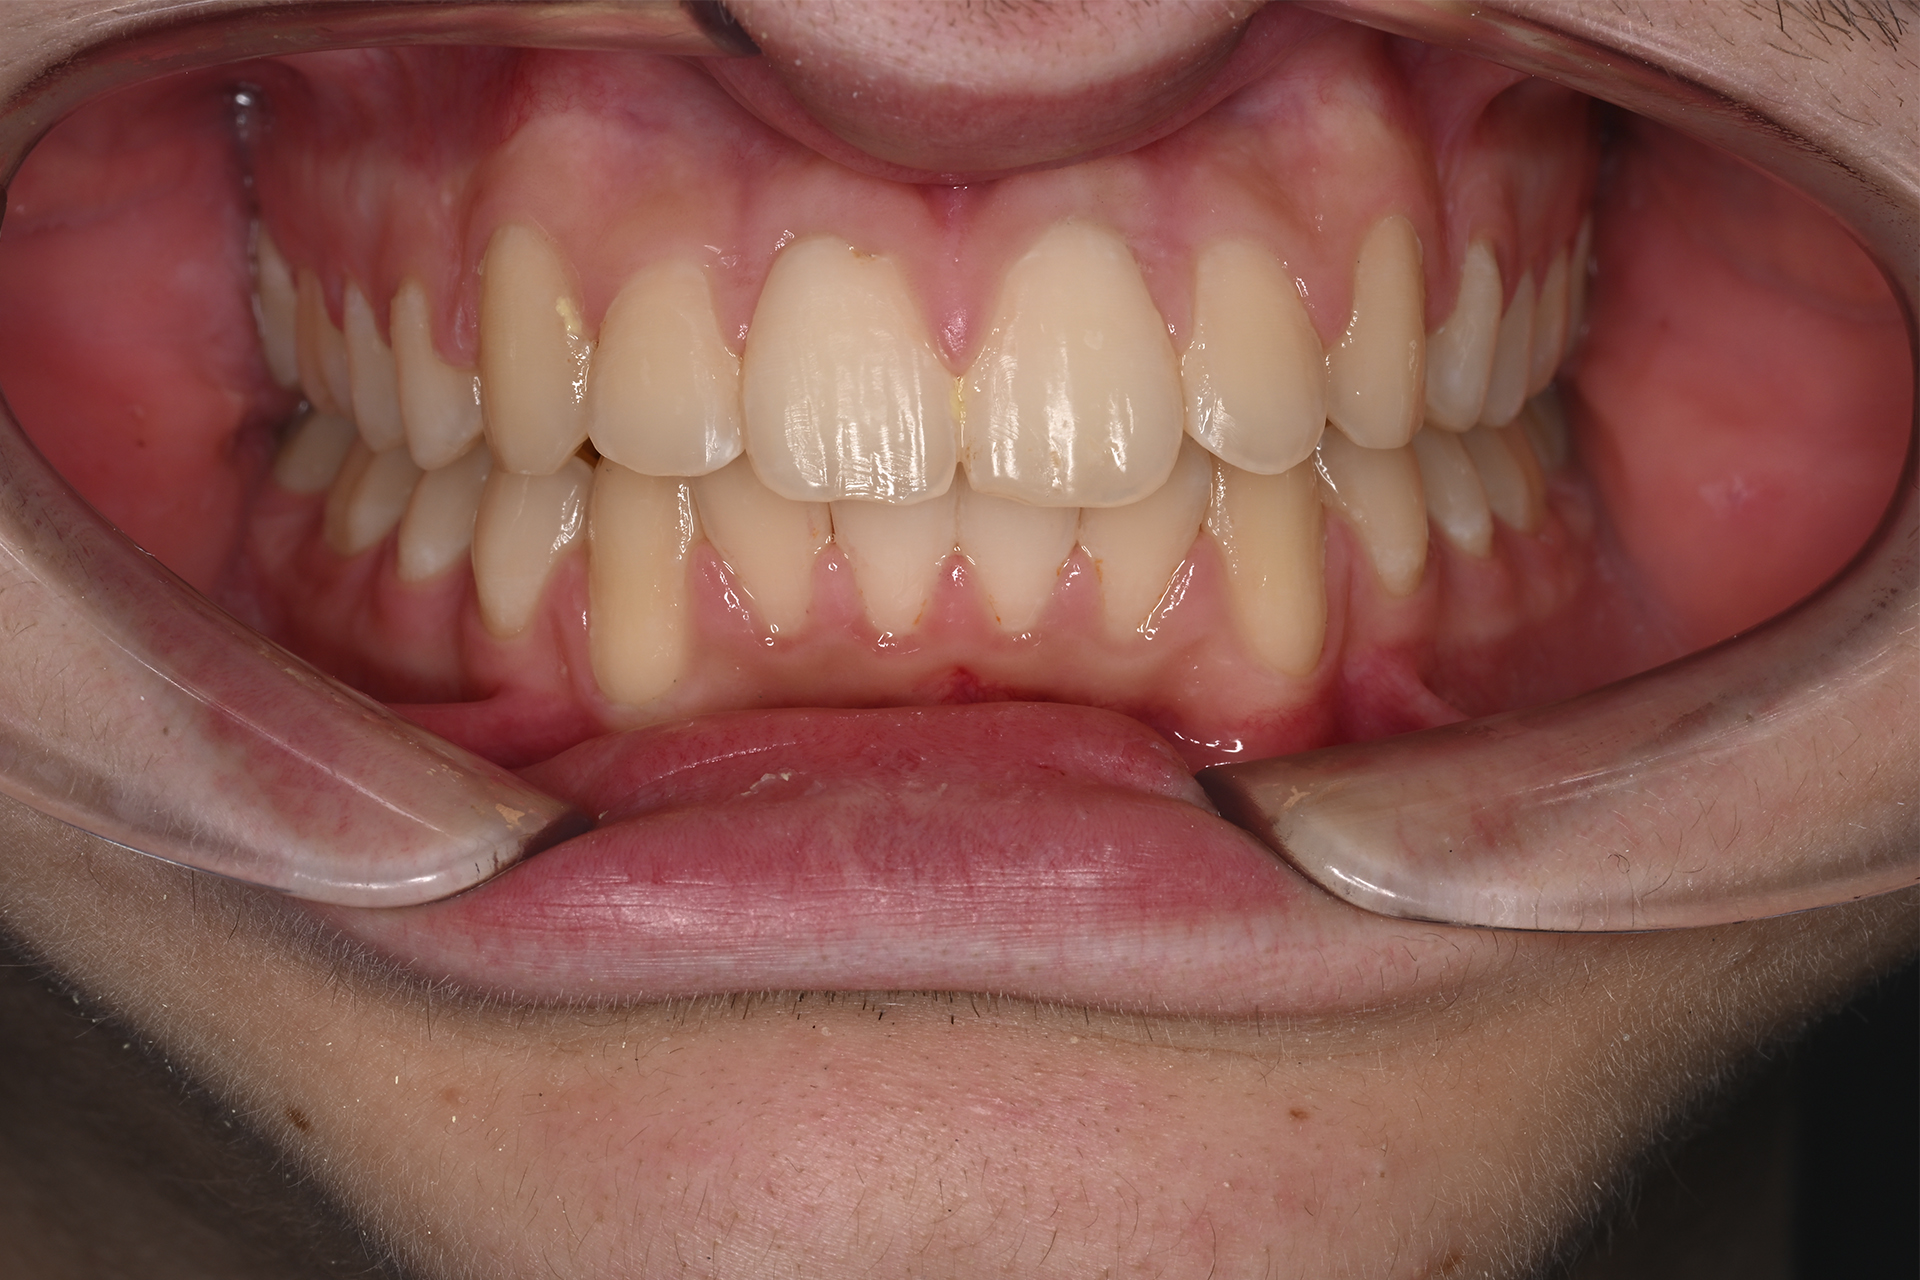

El tratamiento se realizó sin extracciones, utilizando brackets de autoligado para optimizar el movimiento dental. En una primera fase se llevó a cabo la alineación, corrigiendo el apiñamiento; posteriormente, la nivelación permitió coordinar ambas arcadas. Durante el proceso se indicó el uso de elasticos durante el tratamiento para mejorar la relación intermaxilar. En la fase final de detallado se ajustó la oclusión y la estética. Tras un tiempo de tratamiento de 18 meses, se consiguió una correcta intercuspidación, logrando oclusion funcional y y estabilidad periodontal, favoreciendo la salud a largo plazo